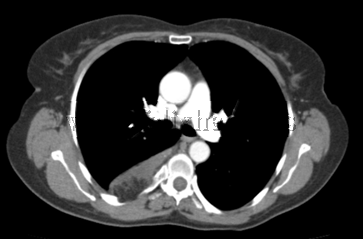

Tumor de mediastino posterior

Neuroma